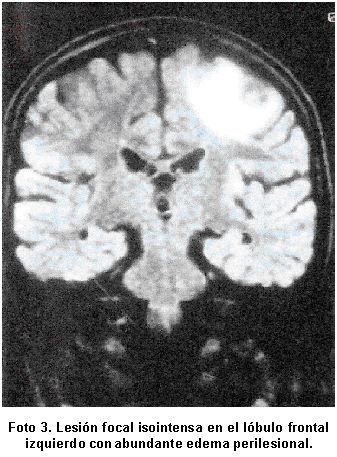

En el Cuadro 3 se describen las lesiones parasitarias halladas en los estudios de neuroimagen, que se localizaron en el lóbulo frontal (Foto 1) y (Foto 2). La TAC evidenció lesiones en cuatro pacientes y sólo en un caso se requirió la RMN para detectar lesión estructural (Foto 3). La tomografía de control reveló lesiones calcificadas en 4 pacientes (80%) y resultó normal en un caso. El estudio electroencefalográfico mostró ondas lentas focales de localización temporo-occipital bilateral en una paciente. La prueba de ELISA fue negativa en todos los casos.